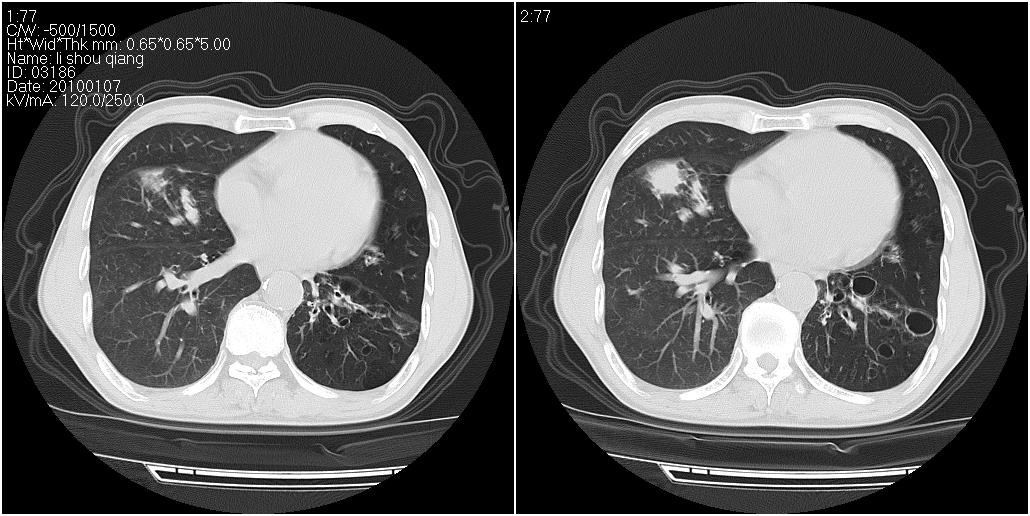

标题: CT24038:男性,58岁。主因咳嗽带血性CT检查。 [打印本页]

标题: CT24038:男性,58岁。主因咳嗽带血性CT检查。

右肺中叶外侧段可见团块影,外形不规则,内见空泡征。左下肺见蜂窝状低密度透亮影,部分层面主动脉旁瘤样突出。考虑右肺中叶外围型肺癌可能性大,左下肺支气管扩张,主动脉弓瘤样突出。

1、右肺中叶病灶内不规则气体影、低密度影,且与胸膜接触面宽,病灶边缘模糊。考虑右肺中叶感染并有脓肿形成。建议抗炎治疗后复查。2、左下叶支气管扩张症。

1)考虑右肺中叶周围型肺癌并癌性空洞形成。2)左肺下叶支气管扩张可能性大。

1、右肺中叶病灶周围有炎性反应,所以考虑感染病灶,建议增强扫描进一步鉴别 2、左肺支扩

右肺中叶外侧段见一不规则的软组织肿块,边缘可见毛刺,并见厚壁空洞,与胸膜分界欠清。另左下肺见多个小囊状扩张区

1、右肺中叶周围型肺癌(内空泡)。

2、左肺下叶支扩,不除外合并肺囊肿。